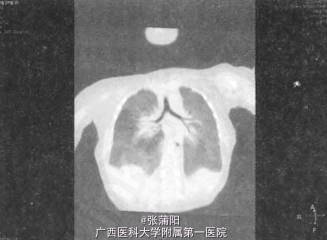

查体:营养发育稍差,体重4.5kg,呼吸尚平稳,无三凹征,胸廓对称,双肺呼吸音基本对称,胸骨左缘第三肋间可闻及三级吹风样杂音。腹不胀,肝脾肋下未触及,肠鸣音正常。 辅查:彩超检查提示:动脉导管未闭、卵圆孔未闭;部分肝脏位置明显上移,不规则,包膜完整光滑,实质回声均匀。CT平扫:右侧胸腔内可见类圆形软组织密度影,其边缘光滑、密度均匀,CT值56HU;CT增强:包块强化均匀,与肝脏一致,且与肝脏分界不清,其内较粗的分支血管走行至门静脉右支;右侧膈肌局限性升高,右上肺未见支气管分支。CT结果提示:①右侧部分性膈膨升;②右肺发育不全;③肝脏右前叶进入胸腔。(图1、2)